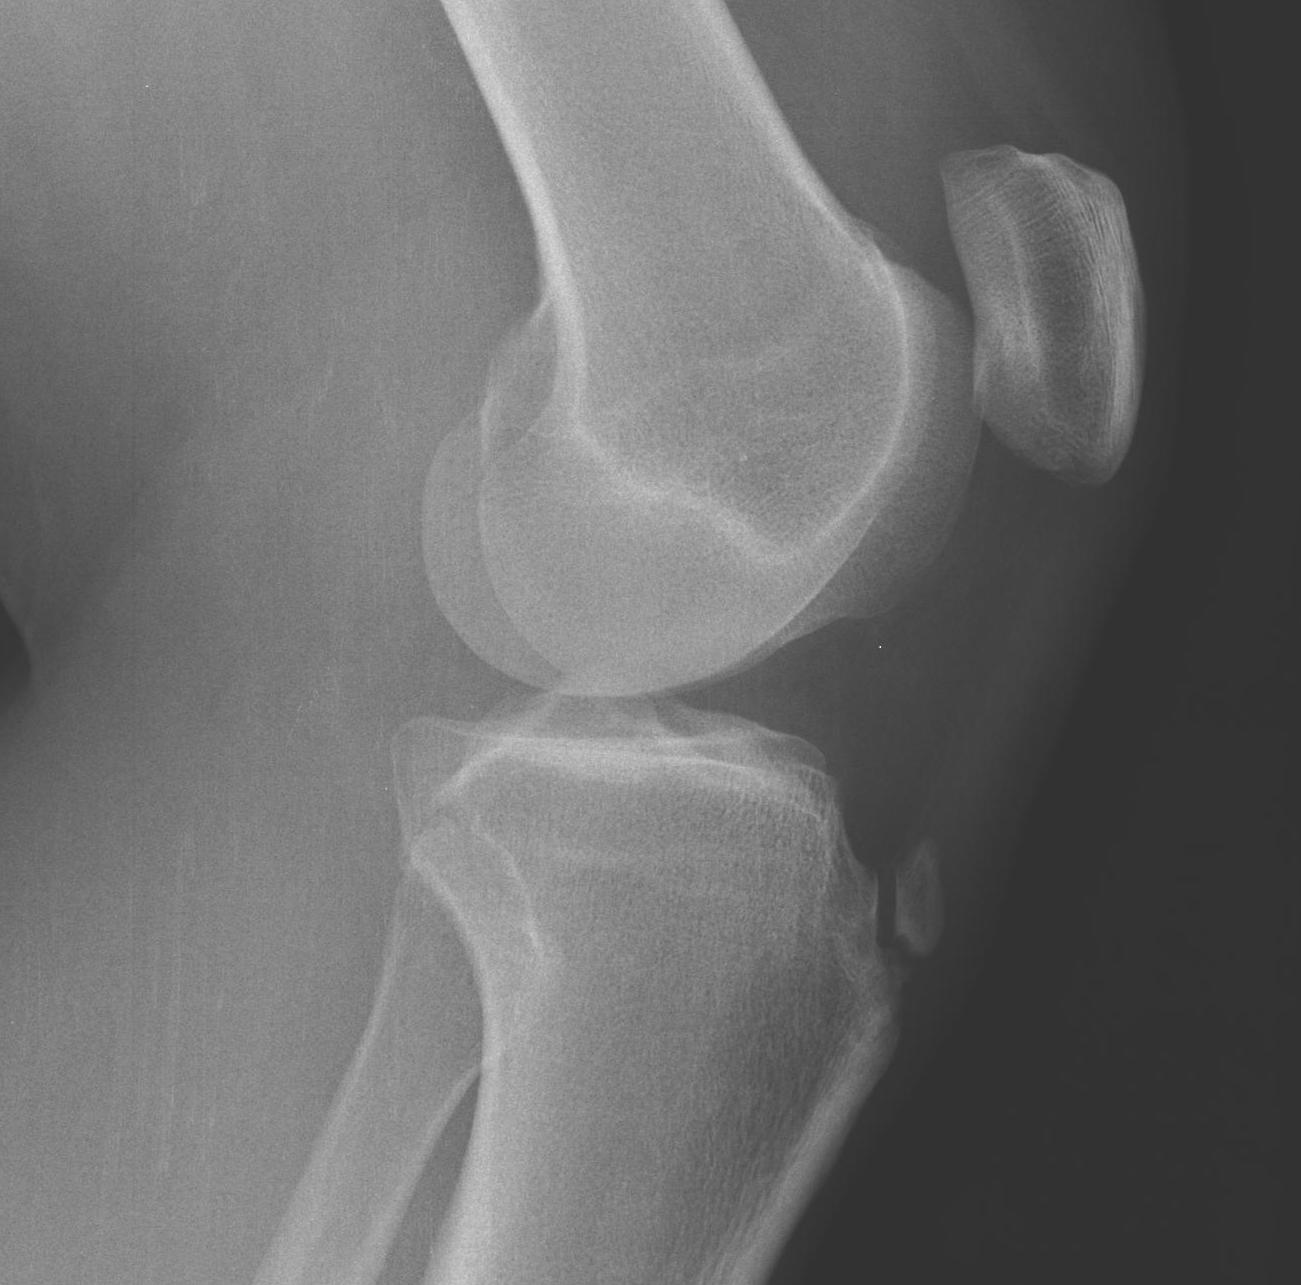

X-ray

Exclude other causes

- enlarged fragmented tibial tuberosity